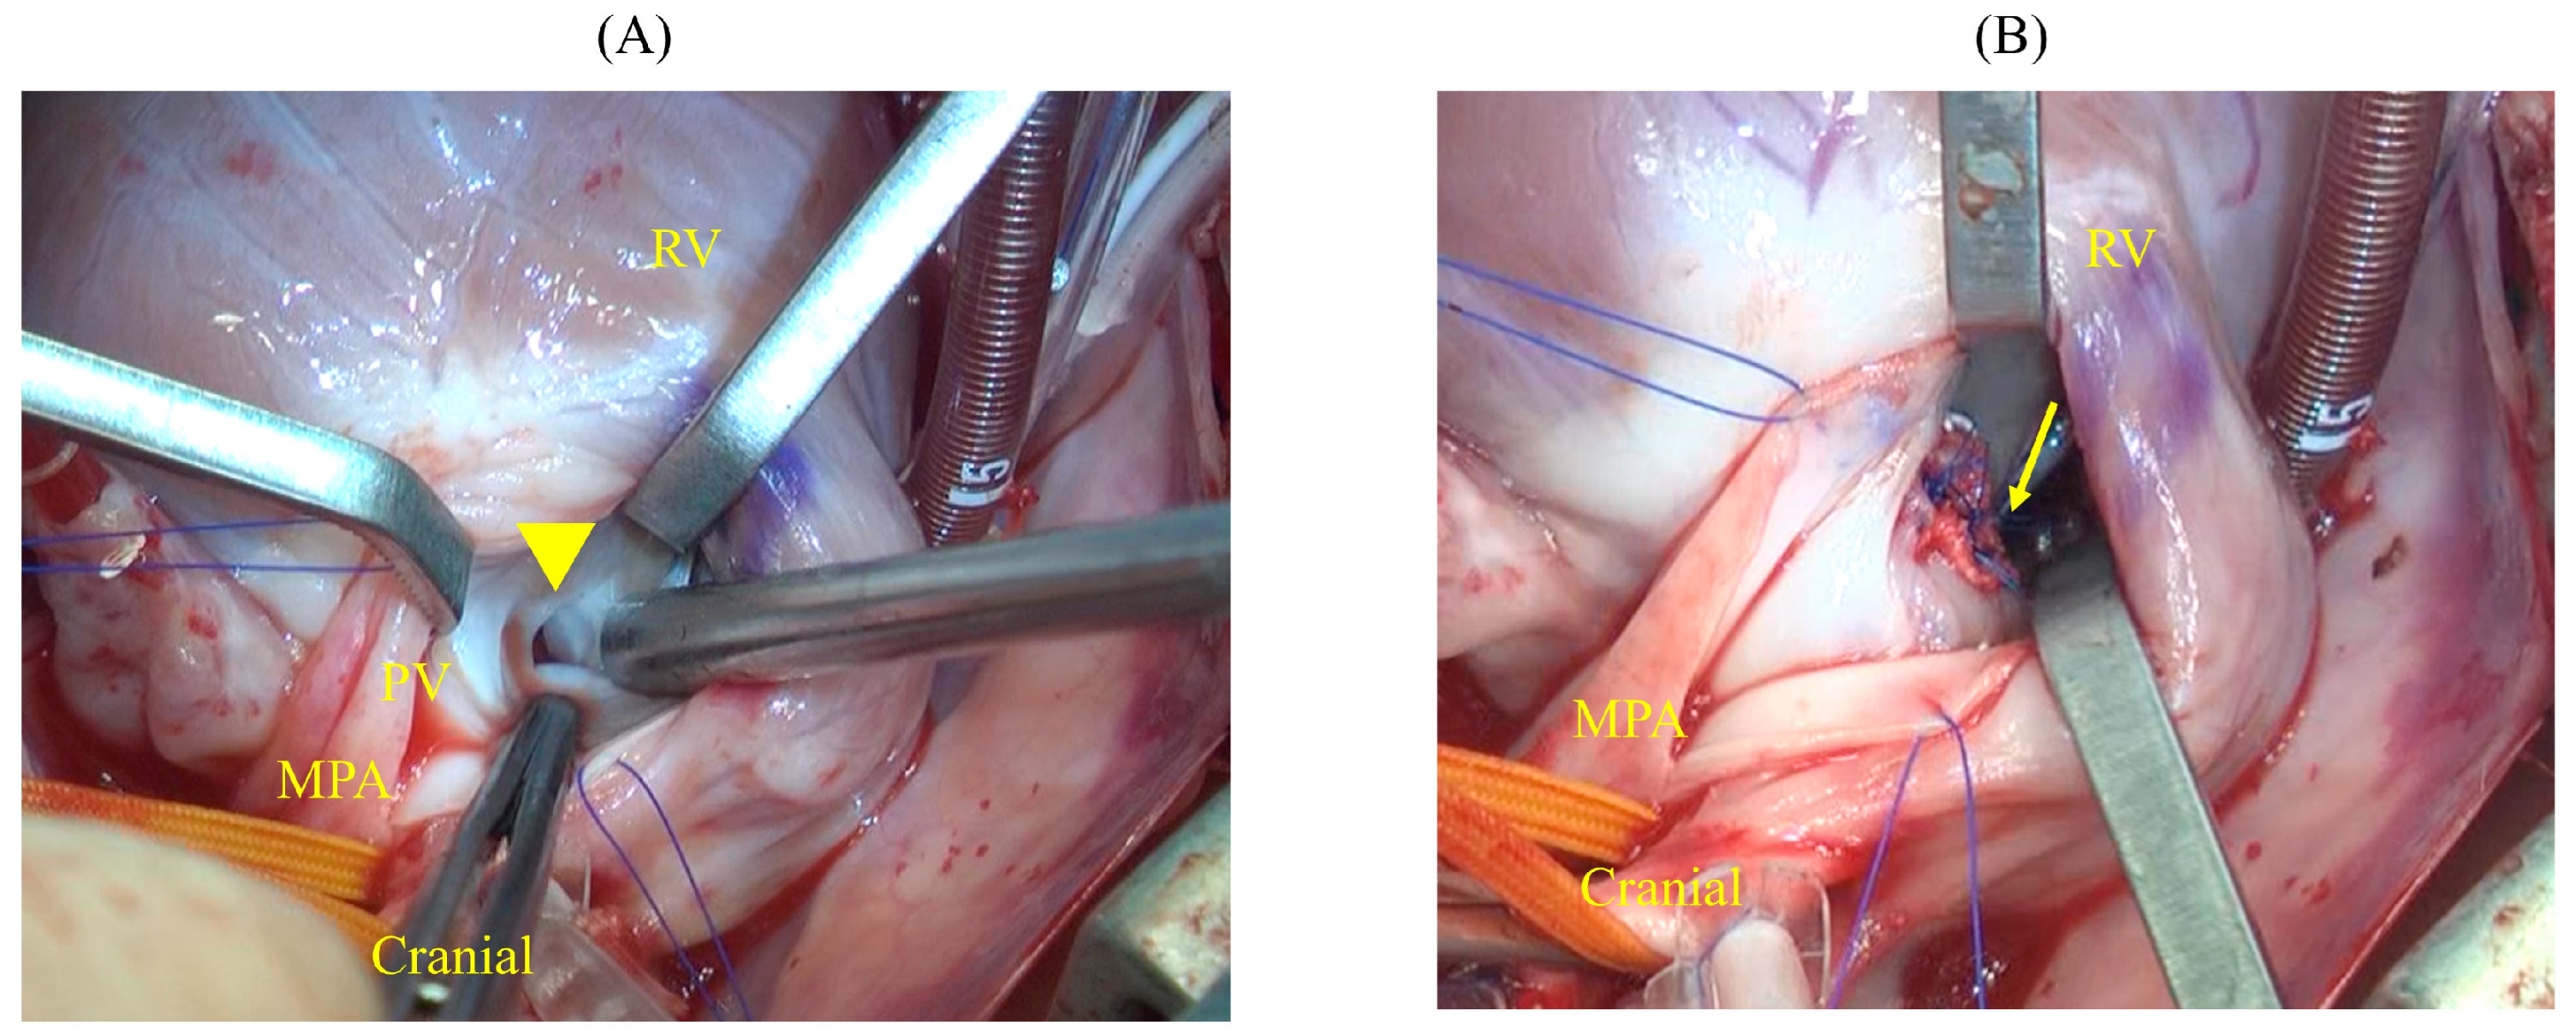

2.2.2. Surgical Technique

- VSD Closure